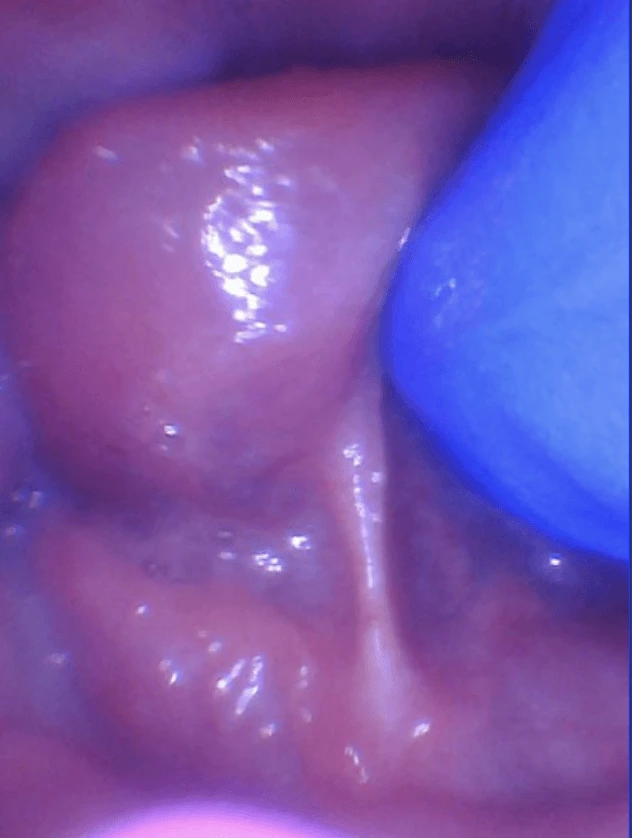

The picture below is of a baby who was a failure to thrive and no one could figure out why. He had a hidden tongue restriction, and after it was properly released, he gained weight rapidly, indicating that was the issue holding him back from thriving.

In these cases, the fascia is too tight underneath the floor of the mouth right under the tongue and can be felt by sweeping a finger underneath. It feels like a tight guitar string or a speed bump underneath the tongue, and this is what is commonly called a “posterior tongue-tie.” If you elevate the tongue by coming from behind and using two index fingers, you can see and feel the tight restriction.